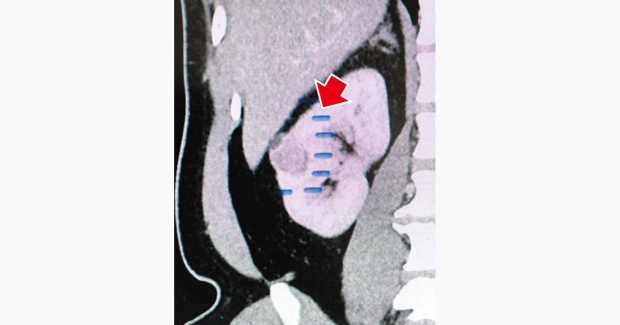

手術時,筆者先用微型超聲波儀器在腎表面勾劃腫瘤的周圍,並落下5針壓力縫線,完全分隔腫瘤與周圍正常腎組織。筆者沿着「欄杆」內圍切除腫瘤時,幾乎沒出血,因為已沒有血液流入腫瘤位置;同時,由於沒夾着主要腎動脈,整個腎臟的血液循環保持正常,術後腎功能完全沒有受損。老朋友的手術非常成功,腫瘤切除邊緣清晰,毋須額外化療或電療,康復速度比傳統方法快得多,只用了5天便出院。這兩年的覆診,腎癌沒有復發,腎功能保持良好,非常感恩。

此手術最創新的是,把止血概念從「夾血管全腎停血」轉為「局部阻斷」。用手按壓是最便利的止血做法,但微創機械臂手術中不能用手按下去,筆者便借用以往做腎穿刺取石手術(Percutaneous Nephrolithomtomy)的經驗,以幼細鋼針精準穿過腎組織,配合縫線形成阻斷屏障。這些針雖然長達6吋,但因為具備腎穿刺技術,加上術中利用超聲波導航,故可確保落針位置準確,既不會刺傷其他內臟,亦不讓腫瘤細胞污染正常組織。

當然,任何新方法都有風險。針長而腎厚,每次穿刺都需要極度小心,落針角度和深度必須準確無誤。這個新術效果理想,至今已為10多名患者進行,病人出血量大幅減少,腎功能保護良好。手術時間雖較長,約4至6小時,但因為沒有「夾血管全腎停血」時間壓力,反而能更仔細和安全地完成。這方法特別適合腫瘤位於腎臟外圍、體積較少的個案。如果腫瘤位置太近中央或體積過大,築「欄杆」難度便大大增加,因此事前必須做詳細立體血管重建電腦斷層掃描(3D reconstruction CT Scan),把腎血管分布像地圖般清楚顯示,才能精準規劃。